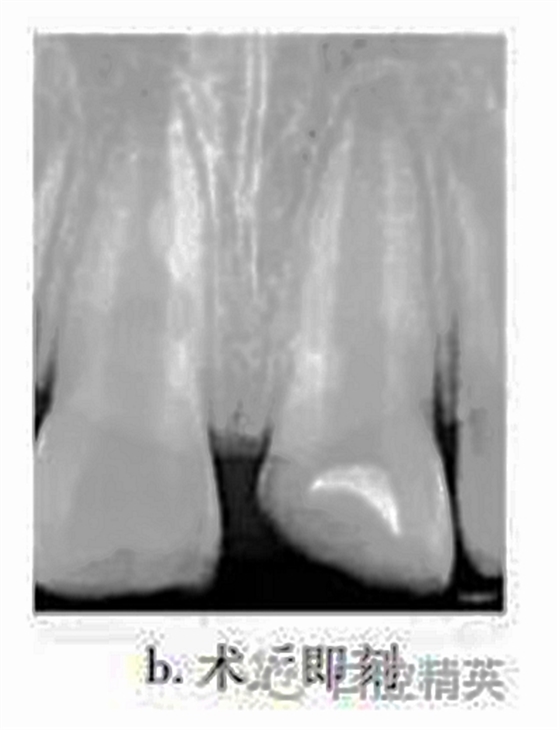

治療:局麻下調(diào)牙合,21揭髓頂,去除可能污染的冠部牙髓,達(dá)根管口處,呈整齊斷面,生理鹽水反復(fù)沖洗以去盡組織碎屑,并用蘸有少許生理鹽水的小棉球置于牙髓斷面壓迫止血,將MTA按操作說(shuō)明要求和生理鹽水按3∶1比例調(diào)和均勻呈糊狀,直接覆蓋在牙髓斷面約1mm,玻璃離子水門汀暫封(圖b)。